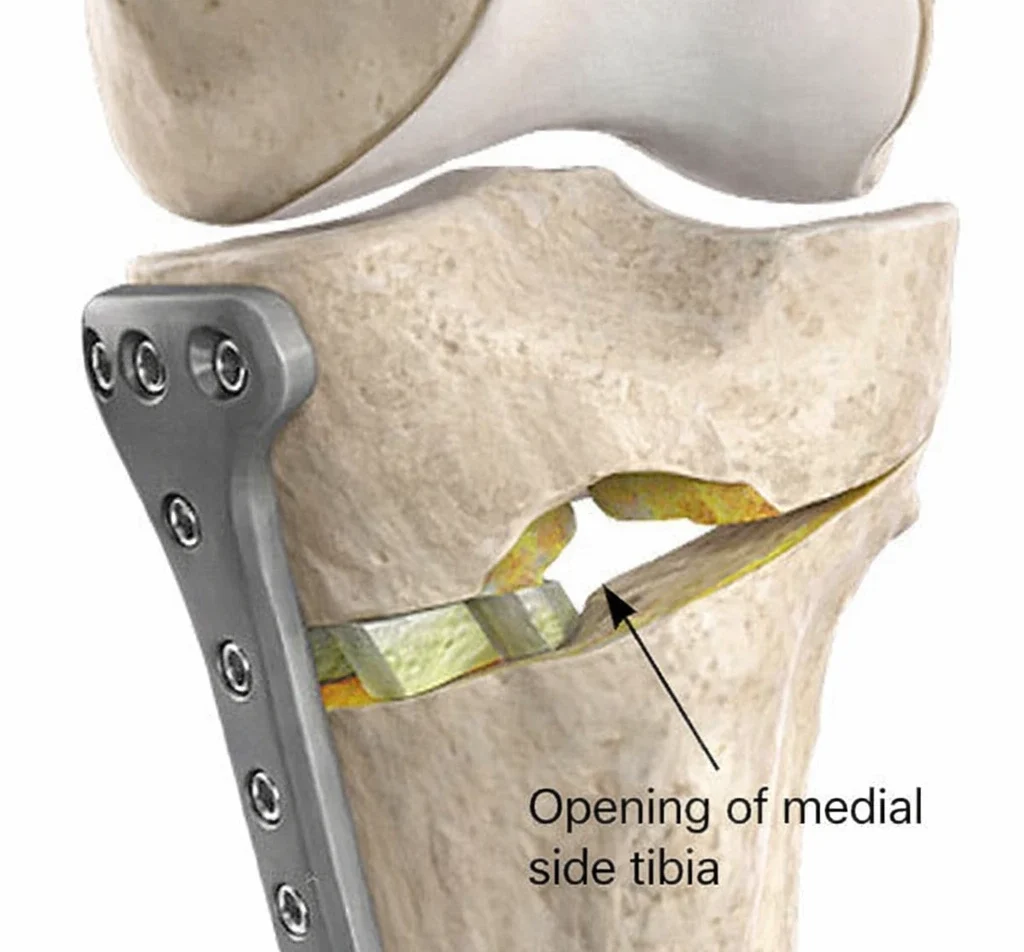

Medial Opening Wedge

In the medial opening wedge technique, a controlled gap is created on the inner side of the tibia. The opened space is stabilized with a plate and screws and is supported with bone graft if necessary.